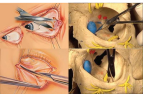

内下壁减压手术

双重睑外壁减压手术

外眦切开的外壁减压手术